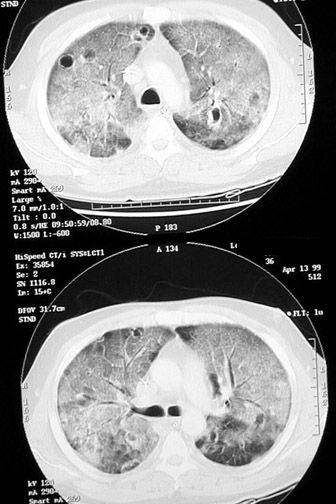

Ground glass appearance on HRCT